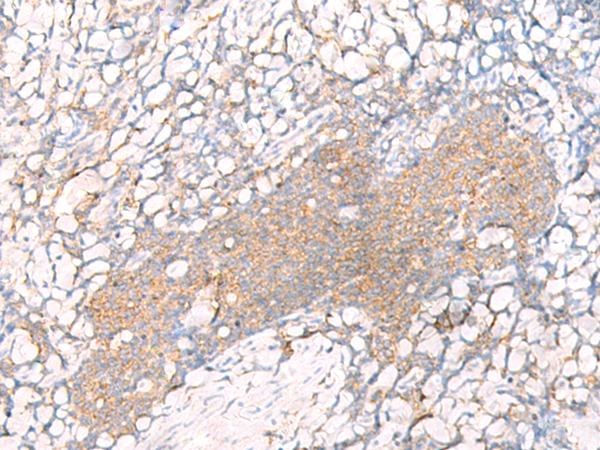

- The image is immunohistochemistry of paraffin-embedded Human tonsil tissue using P13345(HLA-A Antibody) at dilution 1/20. (Original magnification: ×200)